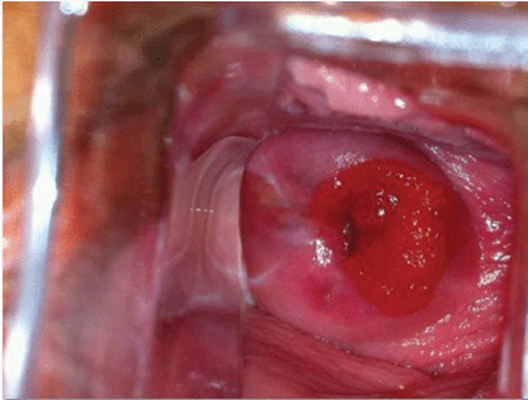

子宮頸糜爛圖片

宮頸糜爛 (8)